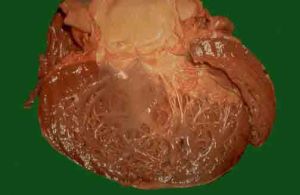

擴張性心肌炎的病理及病理生理

擴張性心肌炎心臟常增大,心臟擴張以雙側心室最明顯,因而稱擴張性心肌炎,心腔擴張較輕者,心室壁稍增厚,病變發展,擴張加重,心室壁相對變薄,心室壁厚度正常或稍增厚。由於心肌纖維化,心肌收縮無力,射血分值下降,半月瓣口可能出現功能狹窄,左右心室擴張,可致房室瓣口相對性關閉不全,血流反覆衝擊致房室瓣膜輕度增厚,心肌病變可擴及心內膜,以及心內局部壓力的升高局部供血不足,可致心內膜斑狀纖維性增厚,約60%的病例有附壁血栓形成。